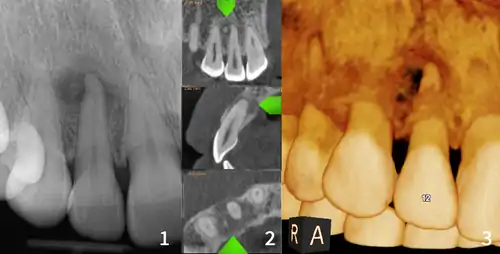

xray and CBCT scans of periapical cemental dysplasia

Diagnosis is important so that the treating doctor does not confuse it for another periapical disease such as rarefying osteitis or condensing osteitis. Incorrect diagnosis could lead to unnecessary root canal treatments. It can be diagnosed by radiographic appearance. Confirming the tooth is vital, as is noting the demographic (African American females).[1][2][3]